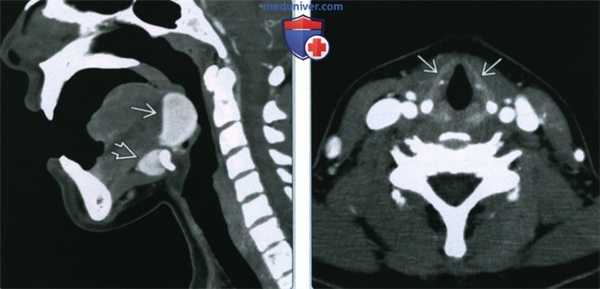

(Слева) КТ с КУ, сагиттальная проекция. Девушка с образованием в области корня языка. Срединное плотное образование, расположенное в области корня языка, вероятнее всею является эктопированной щитовидной железой. Дополнительная эктопированная ткань лежит кпереди от подъязычной кости.

(Справа) КТ с КУ у пациента с язычной щитовидной железой, аксиальная проекция. На уровне щитовидною хряща железа не определяется.

(Слева) КТ с КУ, аксиальная проекция. Подслизистое образование с четкими контурами, расположенное вдоль средней линии дна полости рта. Неоднородная плотность говорит о возникновении зоба.

(Справа) При МРТ Т1ВИ в сагиттальной проекции определяется неоднородное гиперинтенсивное образование, расположенное вдоль средней линии корня языка. Обратите внимание на сужение просвета ротоглотки, а также смещение надгортанника кзади и книзу.